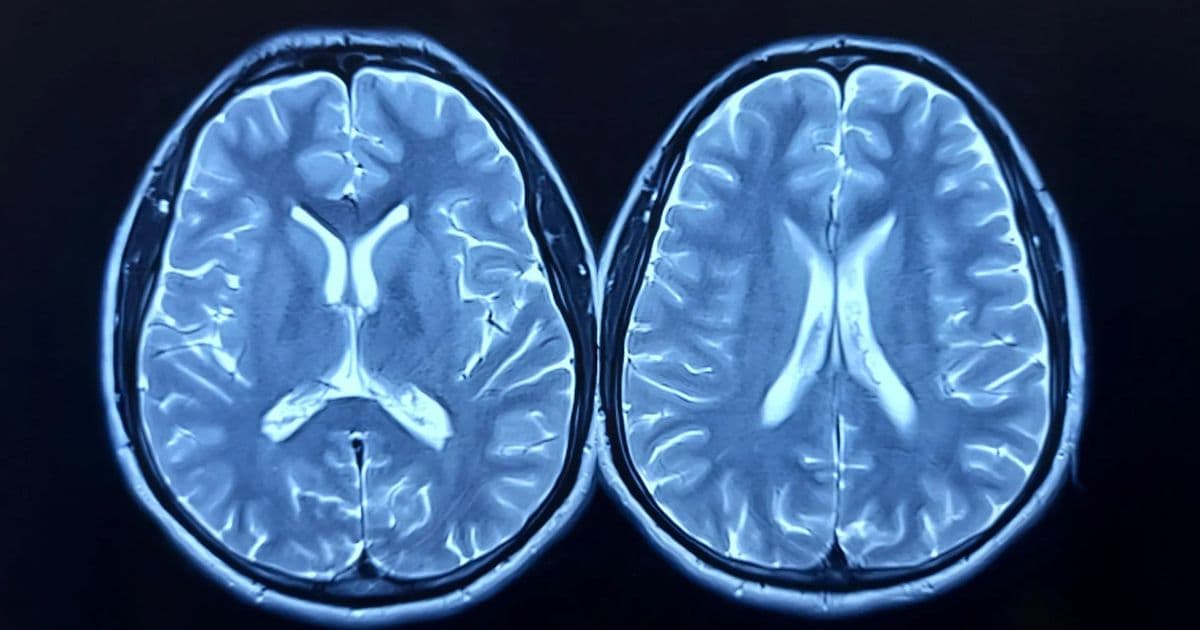

Published in the Journal of Sport and Health Science, the study examined whether regular aerobic exercise could slow or even reverse what scientists call "brain age." Brain age is estimated using magnetic resonance imaging (MRI) and reflects how old the brain appears compared to a person's actual age. A higher brain-predicted age difference (brain-PAD) means the brain looks older, and earlier studies have linked this measure to weaker physical and cognitive performance and a higher risk of death.

Researchers measured brain structure using MRI scans and assessed cardiorespiratory fitness through peak oxygen uptake (VO2peak) at the start of the study and again after 12 months.

After one year, clear differences emerged between the two groups. Participants who exercised showed a measurable decrease in brain age, while those in the control group showed a slight increase. On average, the exercise group saw their brain-PAD drop by about 0.6 years, meaning their brains looked younger at the end of the study. The control group's brains appeared about 0.35 years older, a change that was not statistically significant.